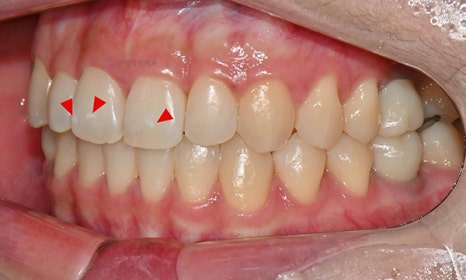

그리고 치아 표면에 브라켓을 붙여서 진행하는 교정치료 후에 장치 주변에 양치질을 제대로 안할 경우 치아에 치태가 쌓이게 되고, 치태가 제대로 제거되지 않으면 치아가 하얗게 삭게 되는 경우가 있는데, 이는 치아의 표면이 부식되는 탈회로 인해서 나타나는 충치의 전단계로 화이트 스팟이 생기게 됩니다.

이런 경우 브라켓을 제거하고 나면 장치의 네모난 베이스 모양이 남아 있고 그 주변부가 초기 단계의 하얀 충치로 남게 됩니다. 치아는 가지런하게 교정이 되었는데 이런 반점치가 생기면 정말 속상합니다. 다행히도 이와 같이 교정 치료 이후에 생긴 반점치는 아이콘 치료의 효과가 좋습니다.